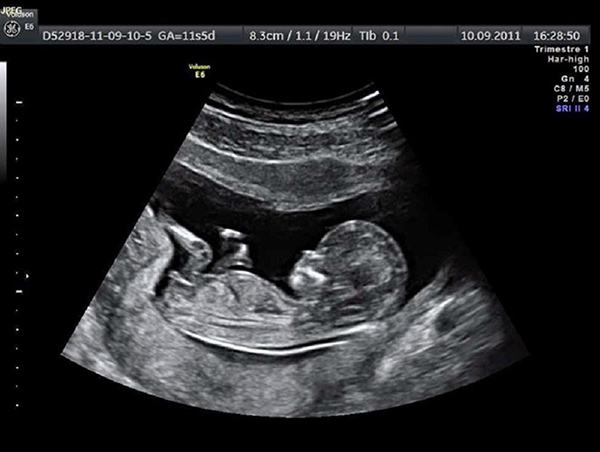

Siêu âm là một phương thức được sử dụng phổ biến đối với những mẹ bầu đang mang thai. Siêu âm gồm nhiều loại như siêu âm 2D, 3D, 4D trong đó thì siêu âm 2D được xem là loại siêu âm đen trắng. Với hình thức siêu âm này cũng giúp các bác sĩ có thể theo dõi được sự phát triển của thai nhi cùng những bất thường xảy ra trên cơ thể bé.

Đây là phương pháp siêu âm được xem và cổ tuy nhiên vẫn được sử dụng trong siêu âm thai nhi hiện nay. Tuy nhiên, với hình thức siêu âm 2D này thì thường chỉ áp dụng cho thai nhi dưới 20 tuần tuổi. Để có thể kiểm tra vị trí của thai, hay những vấn đề bất thường có trên thai nhi.

Phương pháp siêu âm đen trắng này các bác sĩ cũng đo được kích thước trong buồng tử cung của chị em. Kích thước của thai nhi từ đầu đến chân hoặc các bộ phận khác. Với hình thức siêu âm này các mẹ cũng nắm chắc được sự phát triển từng bộ phận của thai nhi.

Ngoài siêu âm thai 2D thì các mẹ có thể theo dõi nhịp tim của thai qua thiết bị chọc dò thai nhi. Tuy nhiên, thiết bị này thường được dùng khi thai nhi đã khá lớn vượt qua 3 tháng đầu tiên của thai kỳ. Thêm vào đó, khi siêu âm thai 2D các mẹ còn có thể nhìn rõ thấy con của mình trong tử cung để biết được bé đang phát triển hết sức tốt đẹp.